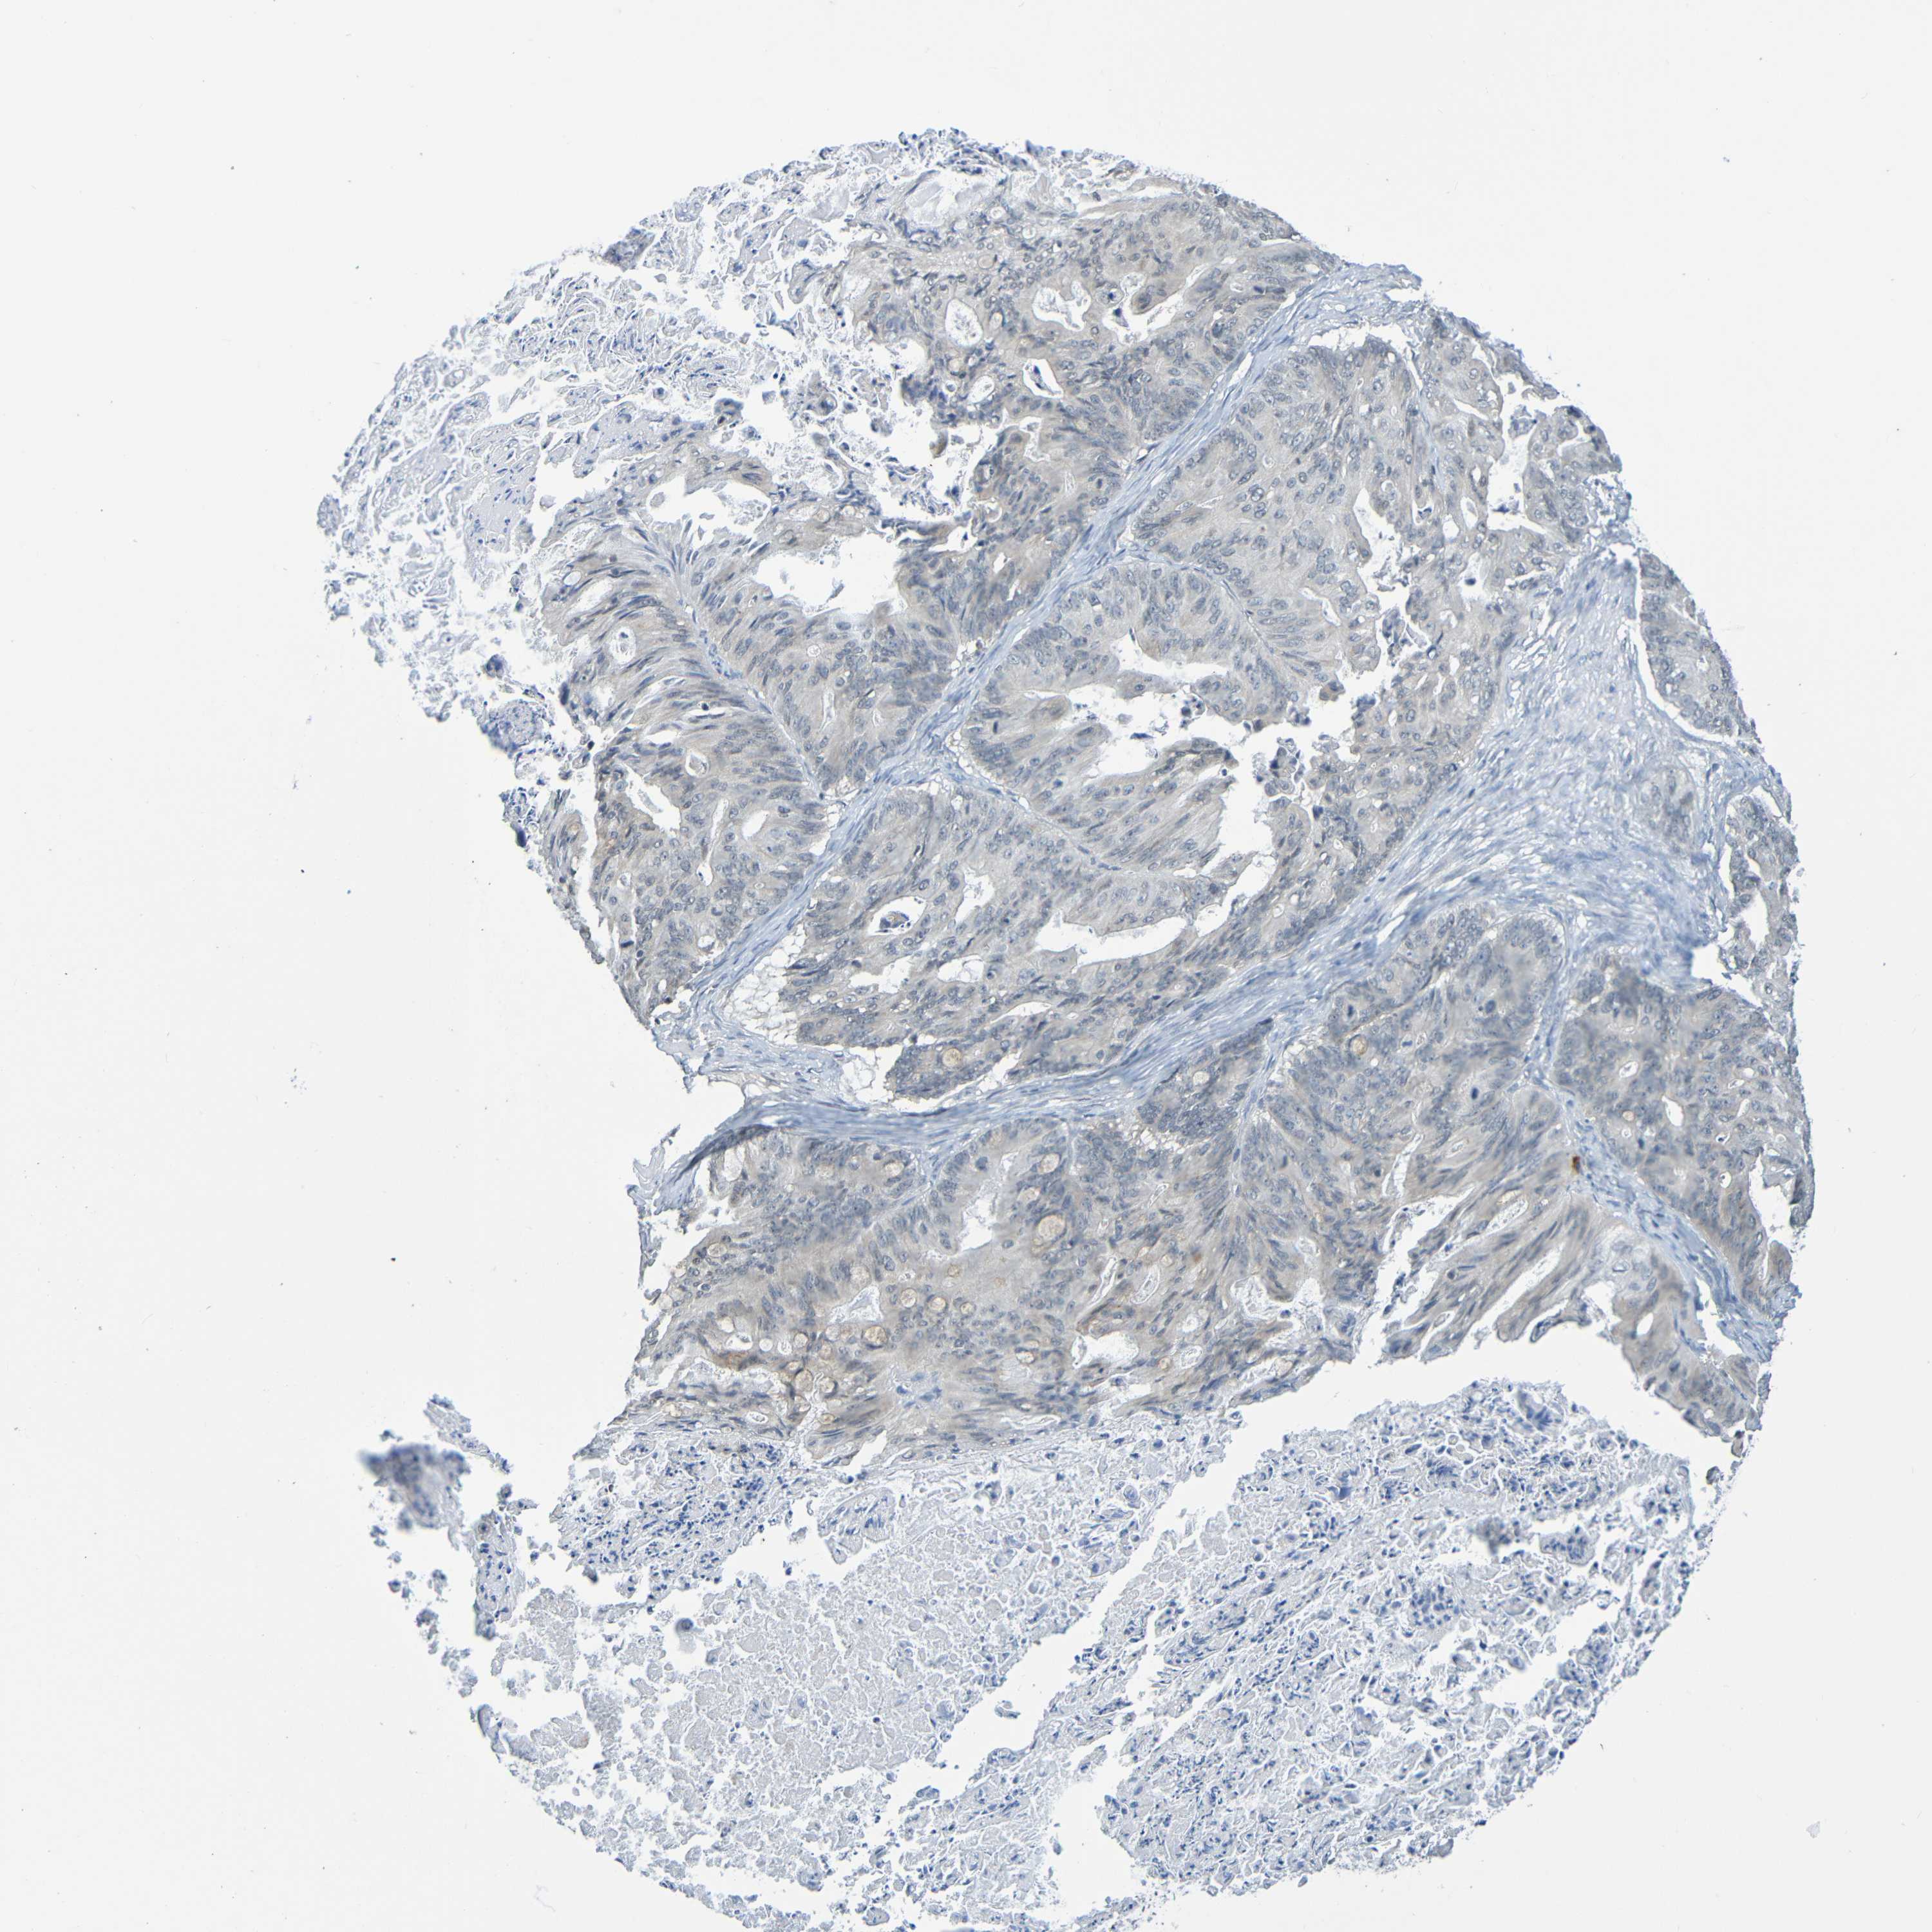

OVARIAN CANCER - Protein expressioni

A mouse-over function shows sample information and annotation data. Click on an image to view it in a full screen mode. Samples can be filtered based on level of antibody staining by selecting one or several of the following categories: high, medium, low and not detected. The assay and annotation is described here.

Note that samples used for immunohistochemistry by the Human Protein Atlas do not correspond to samples in the TCGA dataset.

Antibody stainingi

Antibody staining in the annotated cell types in the current human tissue is reported as not detected, low, medium, or high, based on conventional immunohistochemistry profiling in selected tissues. This score is based on the combination of the staining intensity and fraction of stained cells.

Each image is clickable and will lead to virtual microscopy that enables deeper exploration of all samples and also displays staining intensity scores, fraction scores and subcellular localization as well as patient and tissue information for each sample.

Antibody CAB009405

Staining

High

Medium

Low

Not detected

Intensity

Strong

Moderate

Weak

Negative

Quantity

>75%

75%-25%

<25%

None

Location

Nuclear

Cytoplasmic/membranous

Cytoplasmic/membranous,nuclear

Cystadenocarcinoma, serous, NOS

Carcinoma, endometroid

Cystadenocarcinoma, mucinous, NOS

Carcinoma, NOS